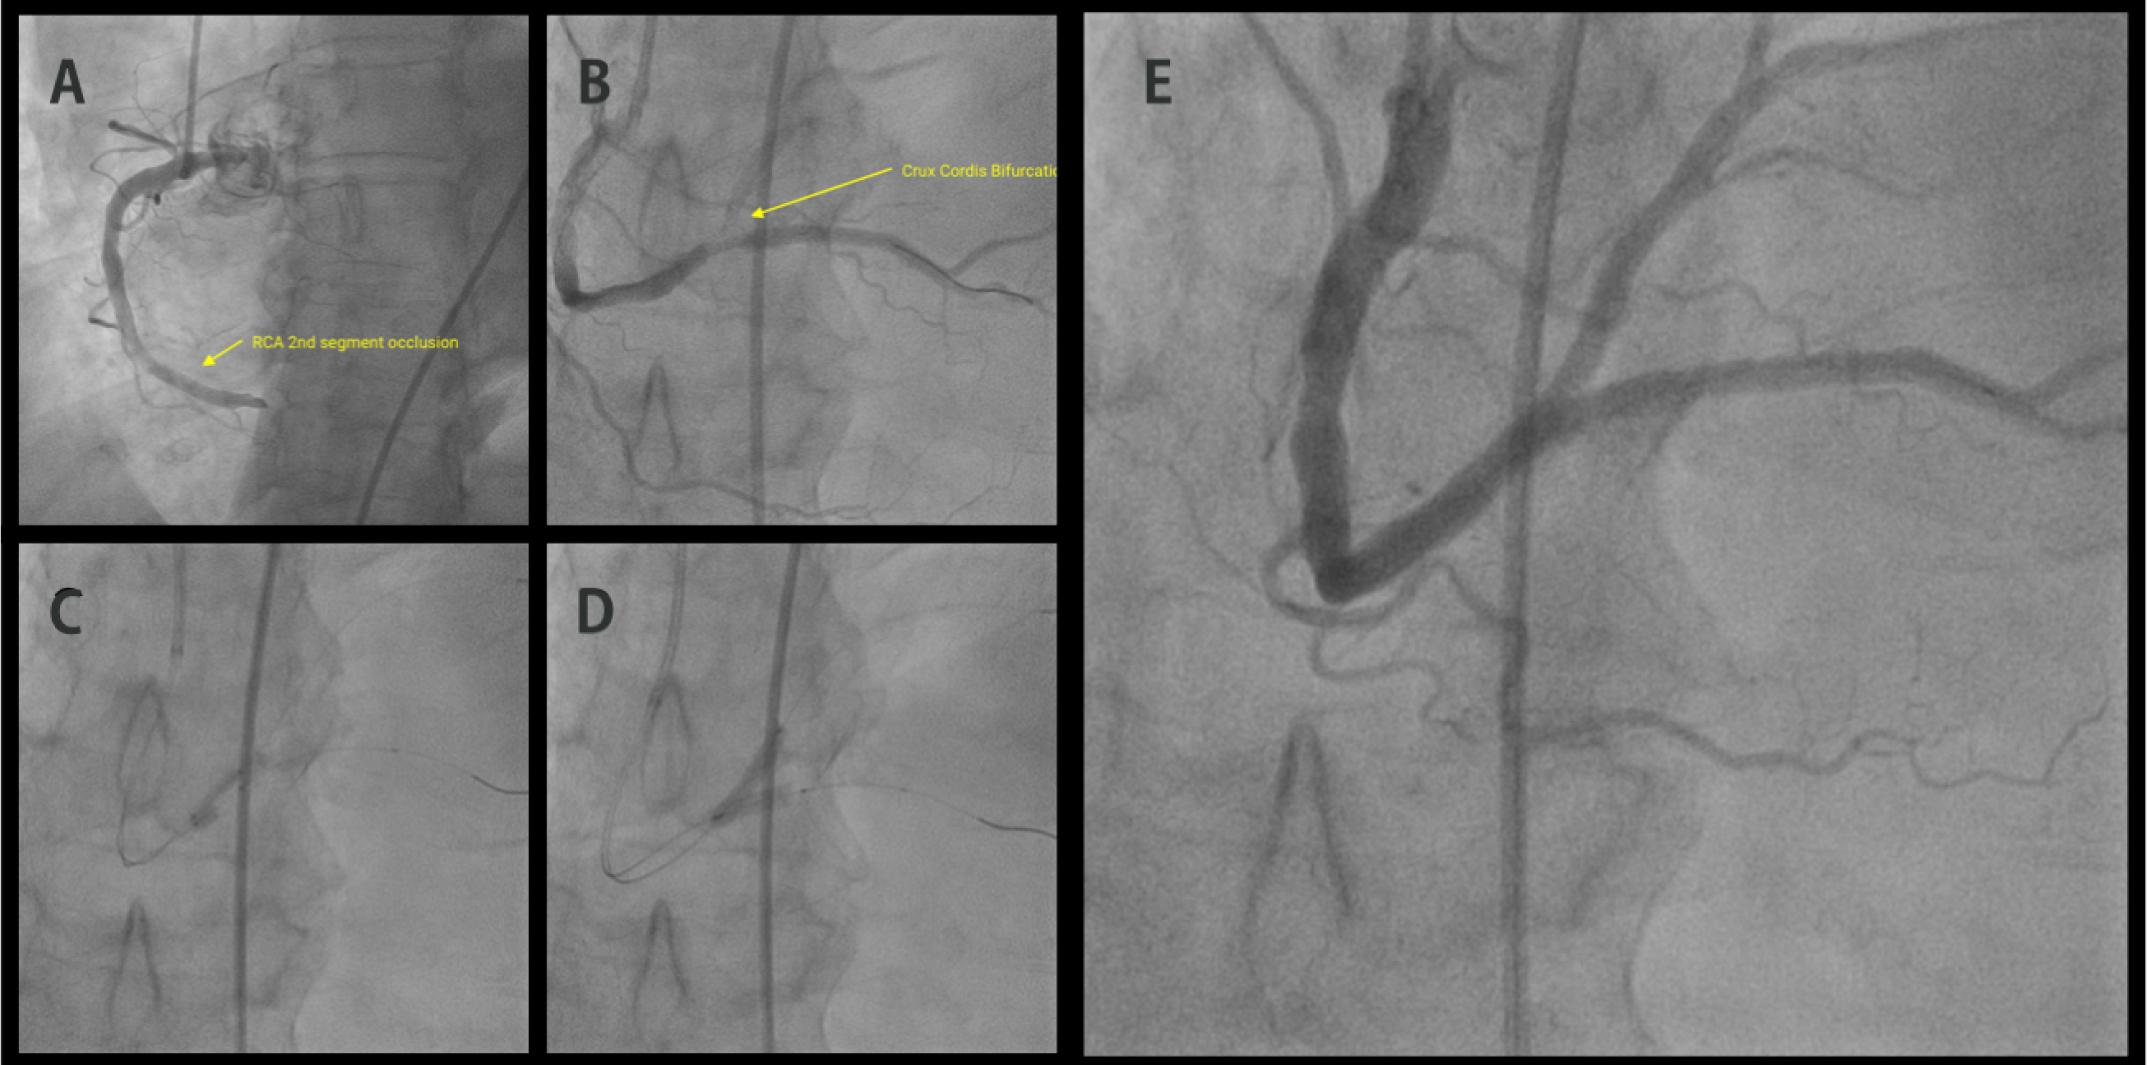

Presenting electrocardiogram: ST elevation in D2,D3, aVF and ST depression in V1-V2, D1,aVL.